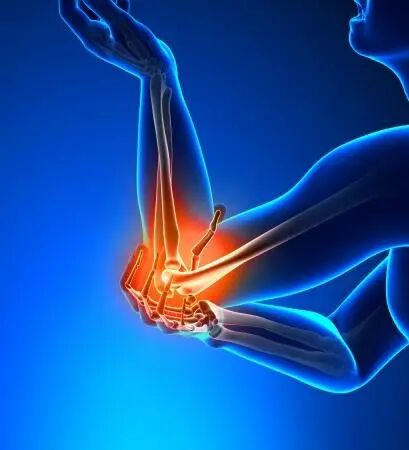

2. 肌腱韧带损伤修复

对于各类急慢性运动损伤,通过PRP治疗可以显著缩短恢复时间,提高修复质量,降低并发症发生风险。